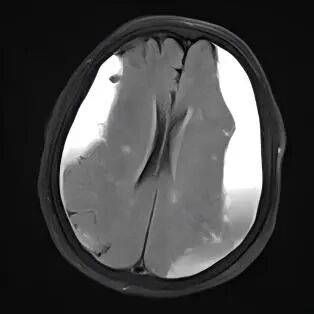

对许多老年人而言,一次轻微的头部磕碰,可能在未来几周或几个月里,悄悄引发一系列变化:走路不稳、手脚无力、记性变差,甚至性格改变,这背后,可能是一种名为“慢性硬膜下血肿”的疾病在悄然进展,它虽起病隐匿、发展缓慢,但会持续压迫大脑,影响正常功能。所幸,现代神经外科的微创手术为治疗此类疾病提供了新的选择,尤其为高龄或身体状况复杂的患者带来了新希望。 微创技术化解高龄手术难题 前不久,一名95岁的高龄患者因双腿无力、多次在家跌倒,并已无法像往常那样站立及行走,家人见状立即将老人送至贵州航天医院就医,通过影像检查发现颅内两侧都有慢性硬膜下血肿。追溯原因,竟是两个月前一次未加留意的头部轻微磕碰。 磁共振影像显示双侧颅内血肿 鉴于患者年事已高,且心肺功能不佳,神经外科团队经过细致评估,决定采用微创手术清除双侧颅内血肿。手术仅在头部开一个极小的创口,置入细软的引流管,将长期积聚的陈旧血液缓缓引出,解除大脑受压,整个过程约30分钟,创伤小,出血少。术后,患者恢复得很快,不久便能自己稳稳站立、独立行走,精神和食欲也好了很多。 疾病知识 慢性硬膜下血肿好发于大脑有一定萎缩的老年人,由于颅腔空间相对增大,头部即使受到很轻的撞击,也可能使大脑表面脆弱的静脉撕裂并缓慢渗血,血液逐渐积聚形成血肿,经过一段“潜伏期”后才压迫脑组织引起相关症状。 如果您或家中的长辈曾有头部外伤史(哪怕当时觉得不重),之后逐渐出现以下情况,请务必留心: ※一侧手臂或腿脚越来越没力气,走路易歪斜、跌倒。 ※反应比以前慢,记忆力明显减退,话变少或表达不清。 ※精神状态不佳,总想睡觉,或性格、情绪出现反常变化。 ※持续或反复的头痛、头晕。 注:本文仅为医疗技术介绍及健康科普知识分享,具体治疗方案请务必咨询临床医生,并结合患者个体情况制定。部分图片来源于网络,如有侵权,请联系删除。 贵州航天医院 神经外科专家简介 廖洪民 神经外科党支部书记、主任,主任医师 临床擅长:从事神经外科专业约30年,擅长脑部病变显微手术、立体定向手术等微创治疗。 贵州省医学会神经外科分会委员,遵义市医学会神经外科分会常务委员,遵义市中西医结合学会理事,中国生命关怀协会脑卒中救治及康复照护专业委员会委员,遵义市脑损伤评价医疗质量控制中心专家,遵义市劳动能力鉴定委员会医疗鉴定专家。 朱家伟 神经外科副主任医师 临床擅长:从事神经外科工作26年,擅长颅脑损伤救治及脑出血微创手术。 遵义市医学会神经外科分会委员、遵义市中西医结合学会脑心同治专业委员会常务委员。 黄建军 神经外科副主任医师 临床擅长:从事神经外科工作20年,对神经外科常见病、急危重症有丰富诊疗经验,熟练掌握神经外科微创手术。 贵州航天医院神经外科简介 • ✦ 基本情况 ✦ • 贵州航天医院神经外科于2008年独立建科,是首批国家卫健委能力建设和继续教育神经外科建设中心,贵州省神经外科介入联盟单位。现有专业技术人员17人,其中高级职称4人,中级5人,初级7人。 科室配备STORZ神经内镜系统、德国莱卡手术显微镜,国产西山开颅动力系统、蛇牌双极电凝、Mayfield头架等颅脑手术设备,以及无创和有创颅内压监护仪、正中神经刺激仪、脑循环康复治疗仪、排痰机、下肢康复训练器、气垫床、多参数监护仪等现代化医疗设备,为病区各种急、危、重患者的观察、监护和治疗保驾护航。 • ✦ 专科特色 ✦ • (一)脑出血微创手术治疗 应用范围:各种病因导致的自发性脑出血(高血压脑出血、脑淀粉样血管病相关脑出血、抗凝药物相关脑出血等)。 技术优势:微创、精准、恢复快。 (二)颅脑病变显微切除术 应用范围:颅内各种占位性病变(脑囊肿、脑肿瘤等)。 技术优势:精确度高、创伤小、恢复快。 (三)颅脑创伤综合救治 应用范围:各种类型的颅脑损伤、创伤性颅内血肿及颅脑创伤并发症、后遗症等。 技术优势:快速精准诊断、个体化手术与监护、早期康复干预,伤者病死率低、并发症少。